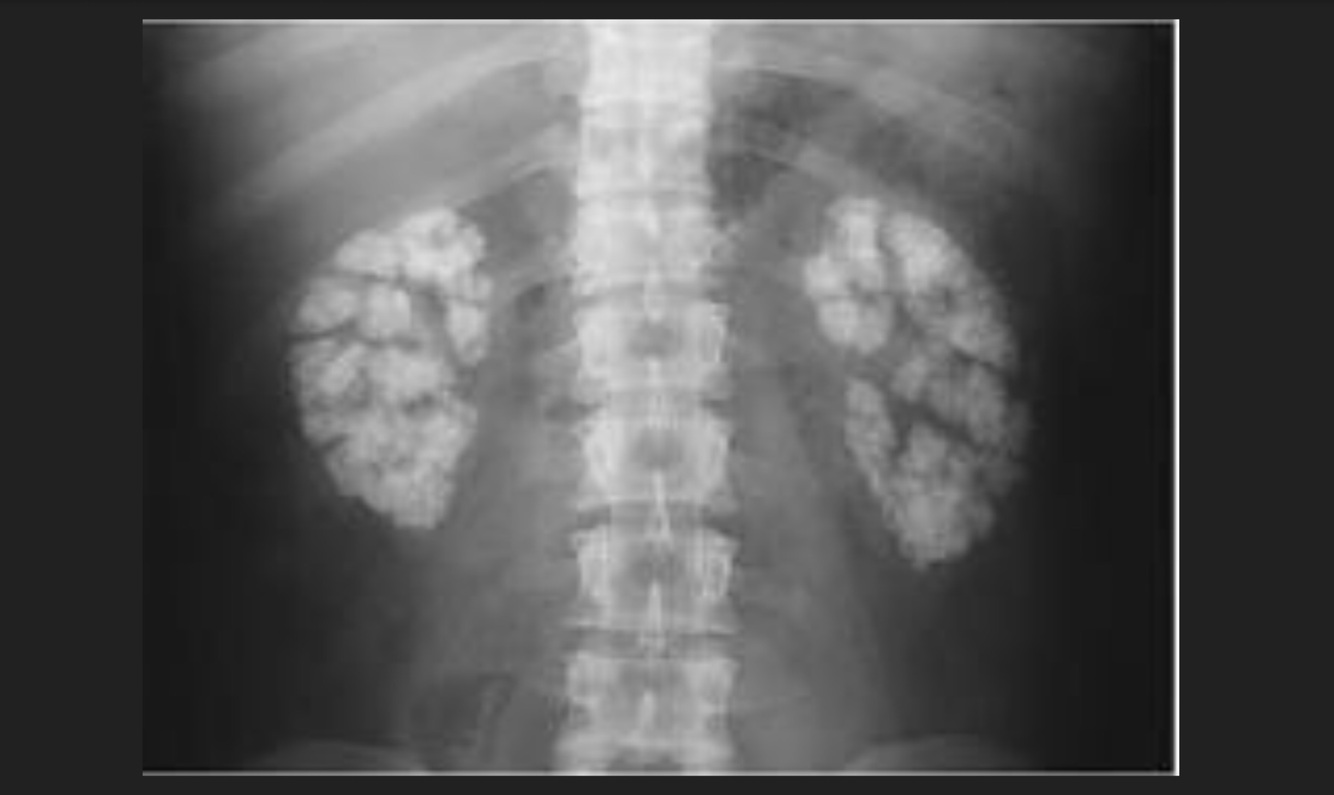

Q

Causa de la insuficiencia renal del paciente

A

Nefrocalcinosis